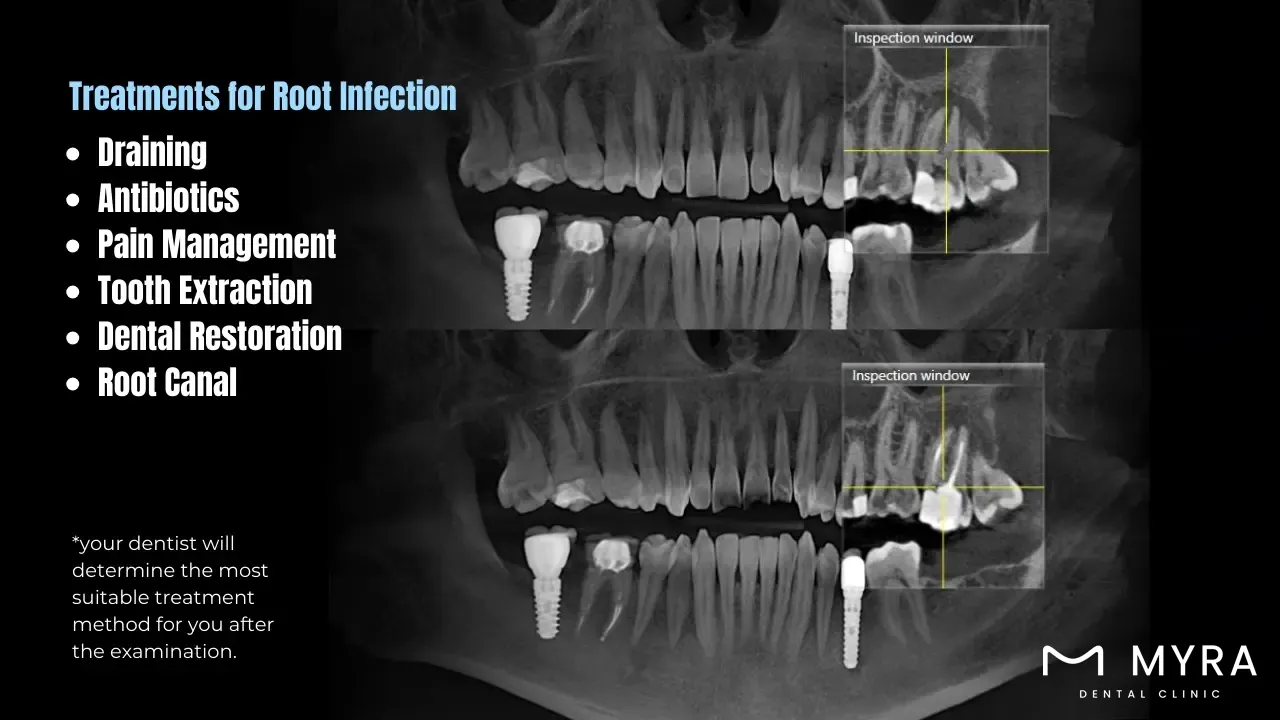

The treatments for Root Infection are listed below.

Draining: Draining an abscess caused by the infection helps reduce pain and swelling. The procedure involves making a small incision to allow the pus to drain out.

Antibiotics: Prescribing antibiotics helps control and eliminate bacterial infection if the disease has spread beyond the tooth to other body parts.

Pain Management: Pain management techniques, including over-the-counter pain relievers or prescribed medications, help alleviate the discomfort associated with a root infection.

Tooth Extraction: Extraction is required if the tooth is severely damaged and has no chance of being saved. Removing the infected tooth with tooth extraction prevents the spread of infection to surrounding teeth and tissues.

Dental Restoration: Dental restorations, such as crowns, bridges, or implants, make the tooth or teeth that were hurt look and work like new after a root canal or tooth extraction.

Root Canal: A root canal treatment involves removing the infected pulp from the tooth, cleaning and disinfecting the root canals, and then filling and sealing the space to avoid further infection.